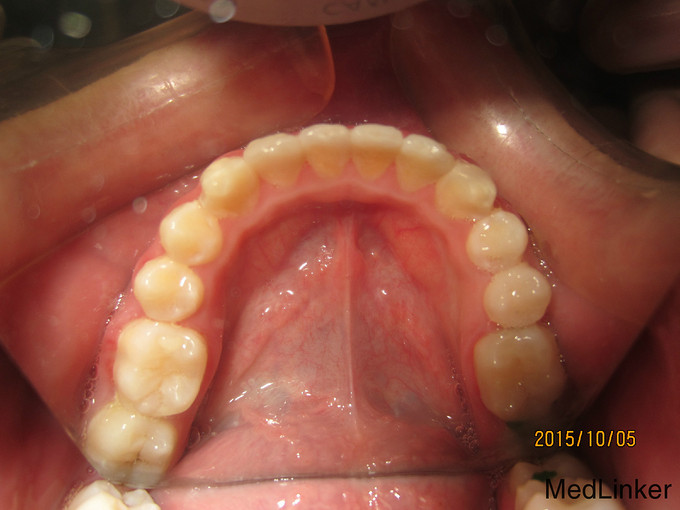

检 查:双侧颞下颌关节开口弹响,开口度一度; 模型测量分析:3度深覆合,上下颌轻度拥挤,spee曲线陡峭,上下颌尖牙尖锐、宽度较小,; 头 颅 侧位片:下颌平面角低角,下颌后缩,余正常; 辅 查:曲面断层片、头颅侧位片,双侧颞下颌关节片

诊断:深覆合、下颌后缩导致颞下颌关节负担加重,引起关节紊乱 治疗:一期:制作合平面导板,戴用一月后关节症状减轻,确定病因; 二期:带用固定矫治器,首先排齐上颌4个月,之后配合平面导板及摇椅弓排齐整平下颌5个月,调整上下颌咬合关系3个月,精细调整2个月,保 持1个月后拆除矫治器,患者自觉关节症状明显好转,制作保持器保持。